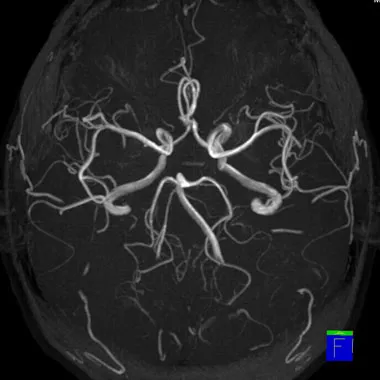

MRI検査は強力な磁石でできた筒の中に入り、磁気の力を利用して体の臓器や血管を撮影する検査です。人に優しく精密な検査が可能で、様々な疾患の診断に威力を発揮します。